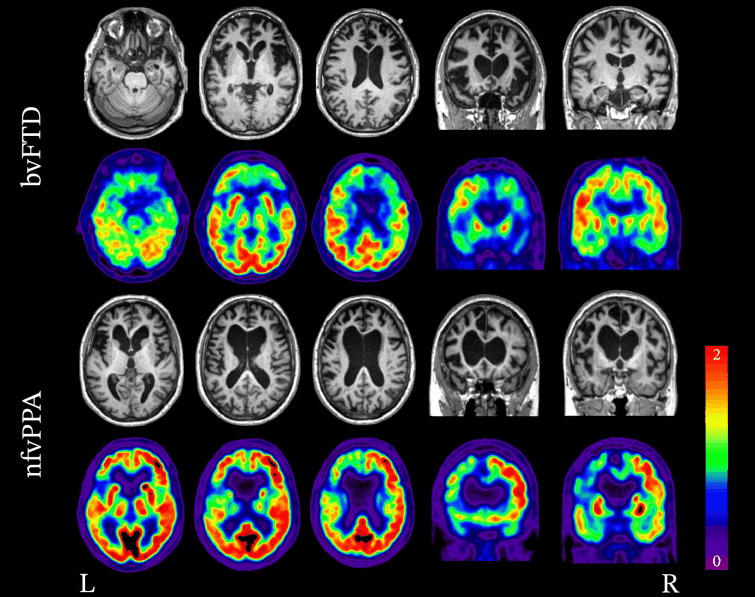

Subtypes of FTD may be determined by observing specific patterns of atrophy and hypometabolism:[104][106][107][108][109][110][111][112]

bvFTD is typically associated with atrophy on structural MRI and hypometabolism on FDG-PET in the prefrontal cortex and anterior temporal lobes, with relative sparing of more posterior regions of the brain, such as the occipital lobe. Disruption in the structural connectivity of the brain, measured using diffusion tensor imaging (DTI), is also a feature.

Primary progressive aphasia (PPA) is associated with relatively focal patterns of atrophy on MRI, and hypometabolism on FDG-PET in the left posterior frontal lobe.

[Figure caption and citation for the preceding image starts]: Neuroimaging patterns associated with behavioural variant FTD (bvFTD) and nonfluent variant primary progressive aphasia (nfvPPA). Structural MRI and FDG-PET demonstrating the variability in patterns of atrophy and hypometabolism in FTD. In the case of bvFTD, significant bilateral frontal lobe atrophy and hypometabolism is seen. In the case of nfvPPA, atrophy and hypometabolism is lateralised and is greatly impacting the left frontal lobe more so than the right.Peet BT et al. Neurotherapeutics 2021 Apr; 18 (2): 728-52; used with permission [Citation ends].